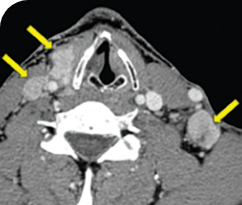

THYROID CANCER PATIENTS WITH METASTATIC DISEASE

BASELINE

AFTER 2 MONTHS OF TREATMENT

56-YEAR-OLD FEMALE WITH MULTIPLE METASTASES3

PATIENT CASE:

METASTATIC, RAIa-REFRACTORY,

PAPILLARY THYROID CANCER1

- 56-year-old female with PTCa that had metastasized to multiple sites, including the brain

- Progression after first- and second-line systemic treatment

- PRa after 4 weeks on VITRAKVI® (larotrectinib); CRa after 8 weeks

- At last assessment, complete response was sustained over an 11-month period

Clinical presentation1

- Patient was assessed to have metastatic, rapidly progressive, RAl-refractory PTC based on imaging that revealed multiple metastatic sites, including the neck, mediastinum, lung, scalp, and bones

- Biopsy of a scalp lesion helped to confirm the PTC metastasis

- Metastases to the brain and liver were observed after progression on systemic treatments

Prior treatments and outcomes1

- Prior treatments included surgery, RAI, a combination of zoledronic acid and sorafenib, external beam radiotherapy, and then lenvatinib

Testing1

- With no further treatment options, the decision was made to perform genomic testing. NGSa testing was performed on a scalp biopsy and revealed an ETV6a-NTRK3a gene fusion. The scalp biopsy had been performed 1 year earlier.

VITRAKVI treatment1

- VITRAKVI 100 mg twice daily orally

Response to VITRAKVI1

- After 8 weeks on VITRAKVI, all target lesions had disappeared, demonstrating a complete response

- The complete response was sustained over 11 months of treatment with VITRAKVI

- Patient experienced Grade 1 fatigue and mild hepatic enzyme elevation

Response in primary and metastatic lesions1

MRIa imagery of the lungs. Arrow indicates large target lesion in left lung.1

SCAN 1: LUNG

MRIa imagery of the brain. Arrow indicates large target lesion in left lung.1